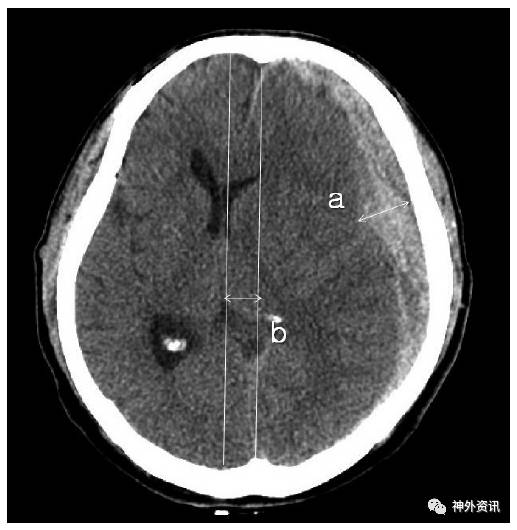

图1. 脑水肿定义为改良前角指数a/b≥33%。

图2. 硬膜下血肿的厚度(a)和中线的偏移程度(b)。